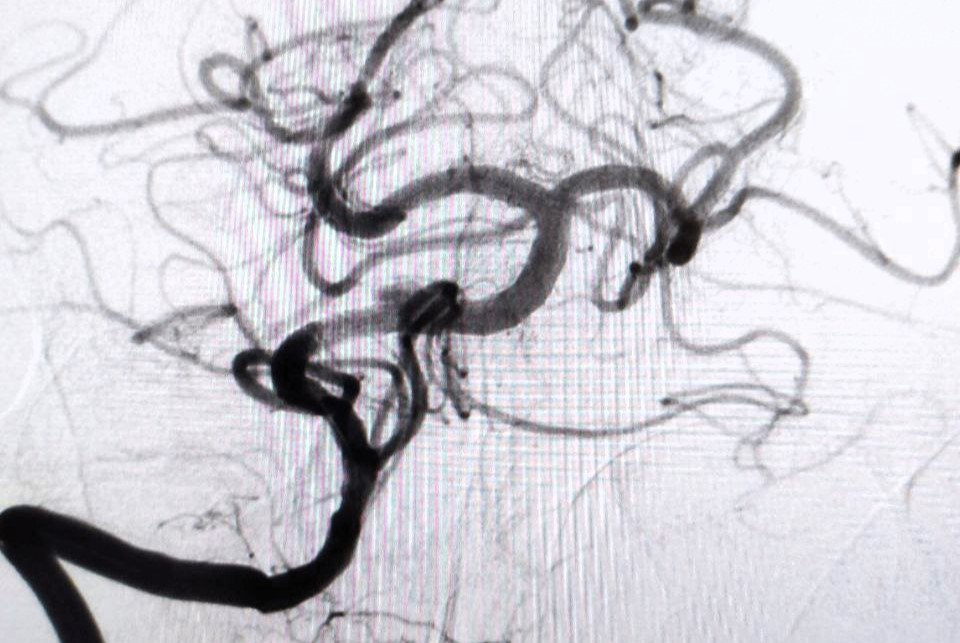

По словам заведующего отделением рентгенохирургических методов диагностики и лечения РСЦ Антона Аналеева, причиной стало образование атеросклеротической бляшки, перекрывшей главную артерию, снабжающую кровью ключевые участки мозга.

Благодаря вовремя поставленному диагнозу пациенту экстренно провели операцию, в ходе которой удалили тромб, а также установили стент.